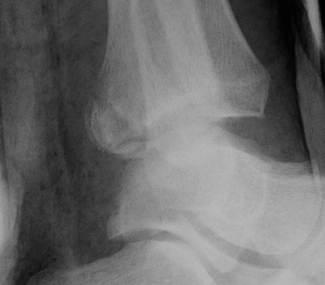

X-ray assessment

3 standard views

AP / Lateral / Mortise

Mortise

- AP with foot internally rotated

- should be symmetrical space around talus

| Increased tibio-fibular clear space | Overlap | Increased medial clear space |

Medial border of the fibula Lateral border of the posterior tibia (incisura fibularis) Measured 1 cm above the plafond |

Overlap of the fibula and the anterior tibial tubercle

Medial talus to lateral medial malleolus |

| <5mm AP and mortise |

> 6 mm AP view > 1 mm mortise view |

< 4mm Equal to superior clear space |

| Syndesmotic injury | Syndesmotic injury |

Deltoid ligament injury Lateral talar shift |

Lateral talar shift / increased medial clear space / deltoid ligament injury

Tibia / fibular overlap < 1mm / syndesmotic injury